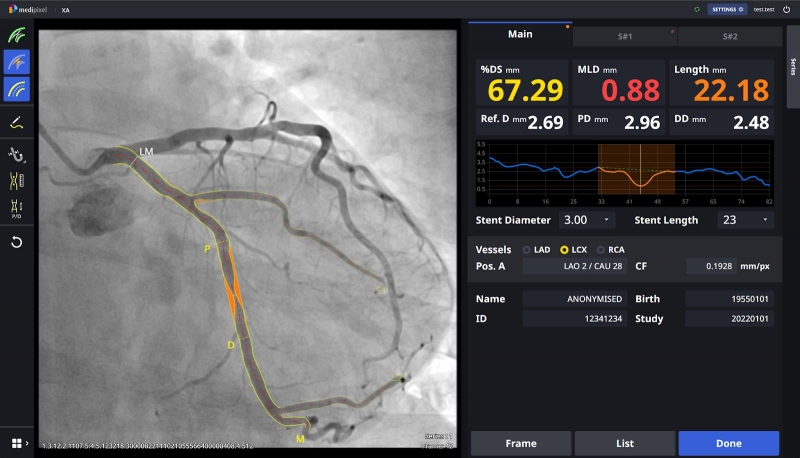

Medipixel XA는 관상동맥 주혈관은 물론 주혈관에서 뻗어나온 분지혈관 여러 병변을 동시에 찾아 협착수치를 제시해주는 기능을 갖췄다.

Medipixel XA는 협착이 의심되는 혈관을 자동으로 검출하고, 의심 부위 위치 정보와 의심 정도를 수치로 표기해준다.

혈관 분할, 병변 분석 과정이 1~2초만에 끝나도록 완전 자동화해서, 시술실 안에서 의사를 보조해 스텐트 시술 등에 실시간으로 활용할 수 있다는 점이 특징이다.